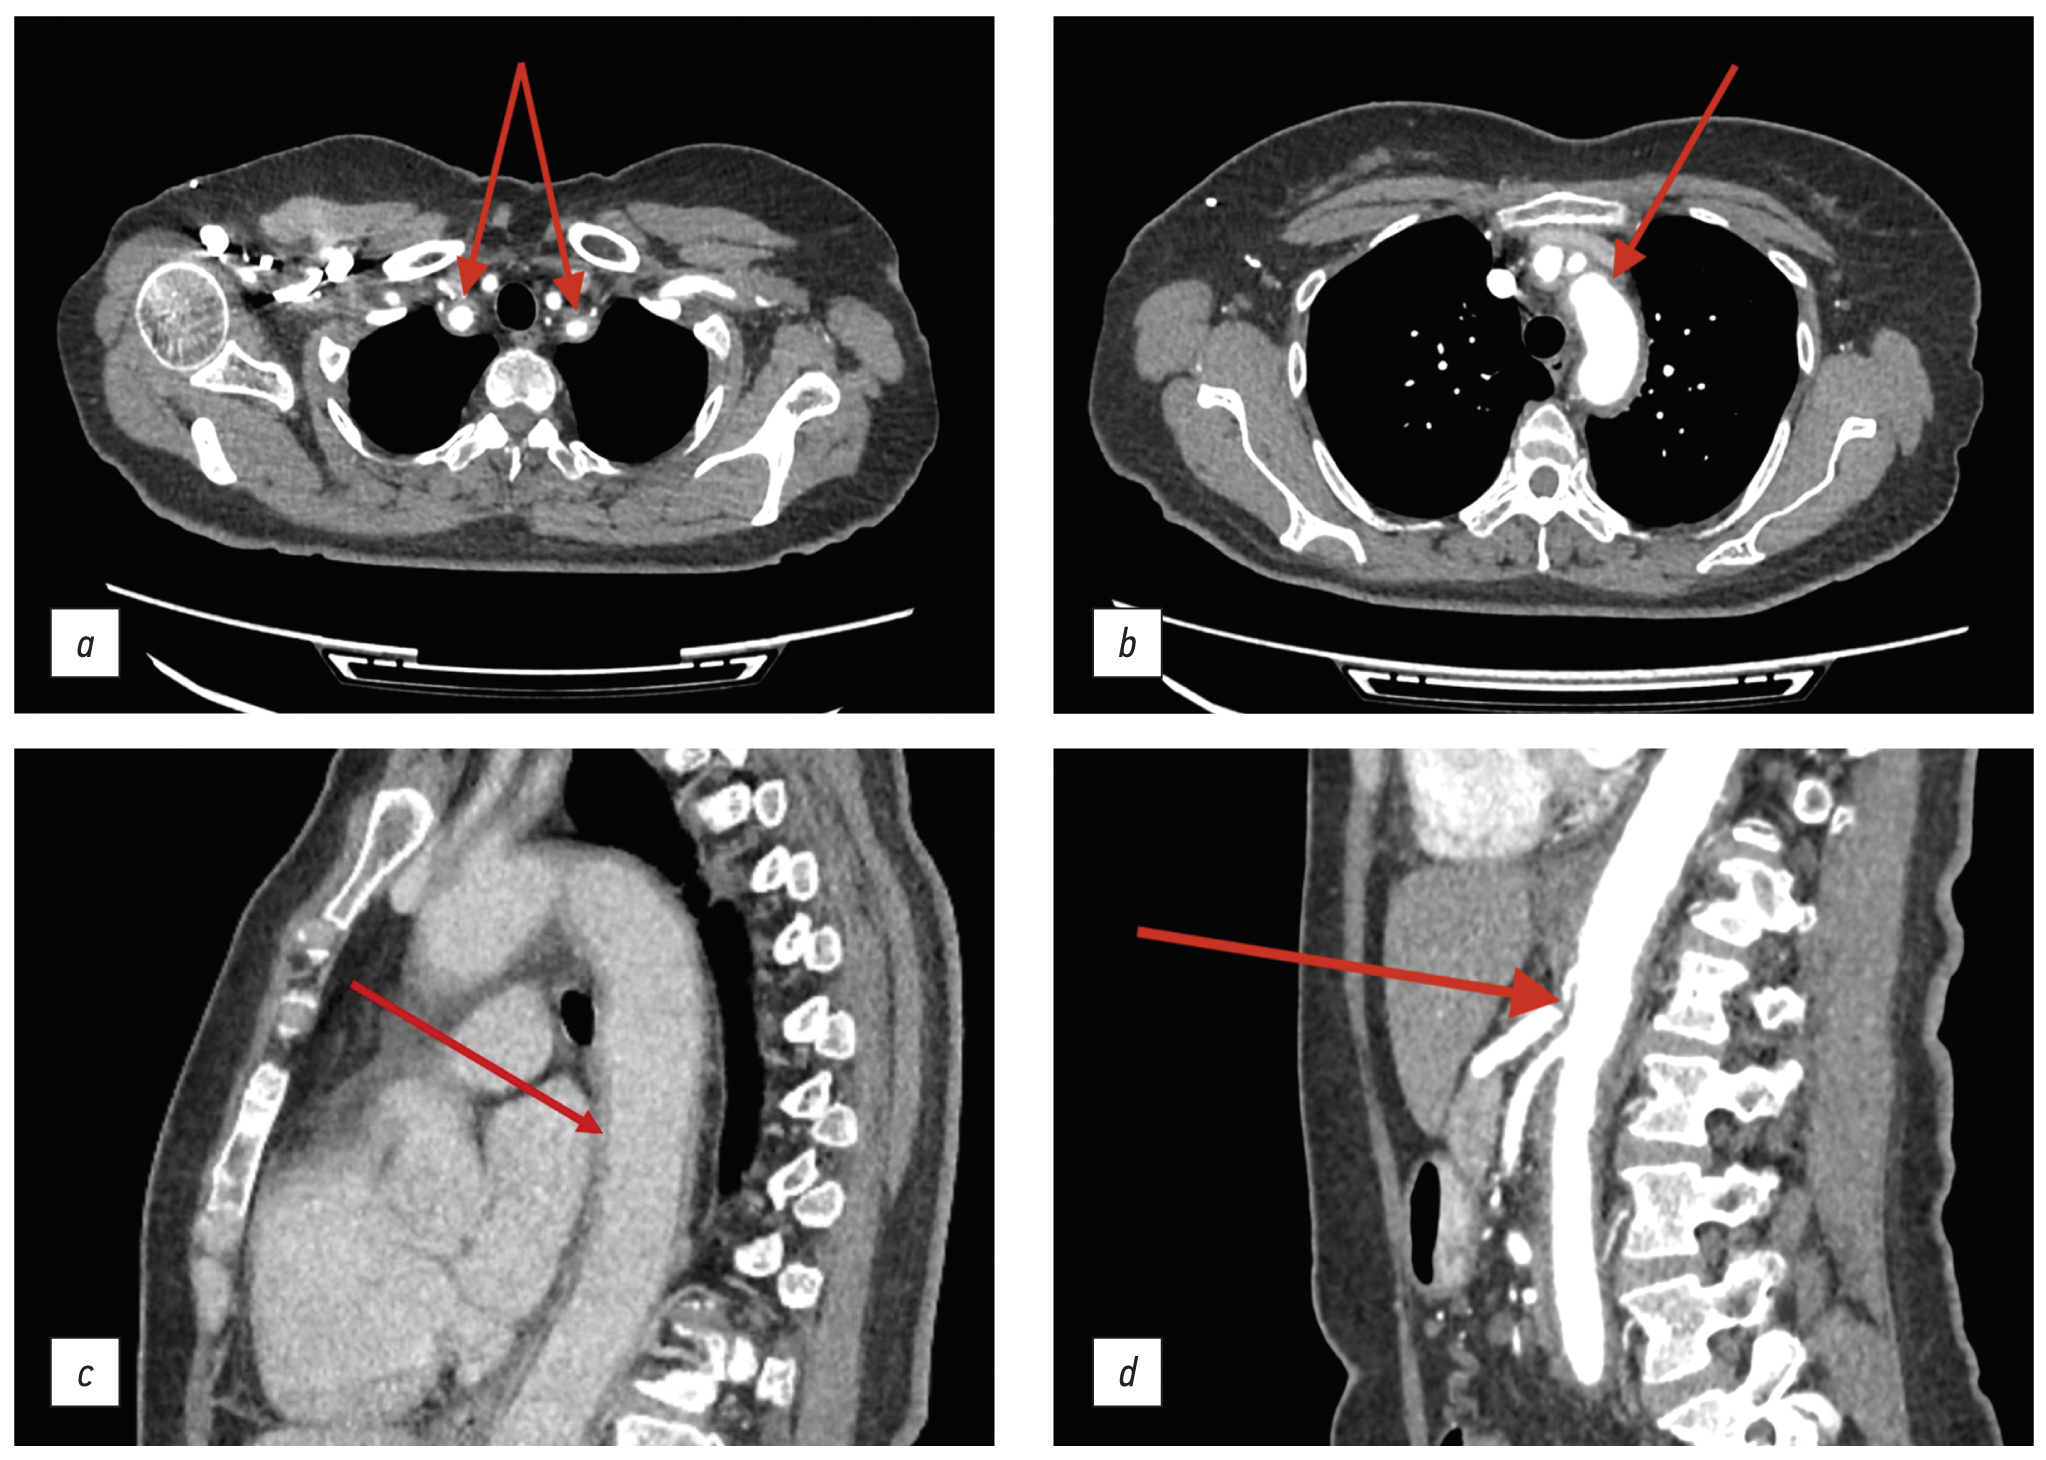

The follow-up thoracic and abdominal CT with i.v. contrast showed pleural thickening in the apical area of the lungs; aortic wall thickening up to 5 mm and lamellar, poorly defined contours of the aortic wall were remarkable, and they actively accumulated the contrast agent. Similar changes were visualized in the brachiocephalic trunk, subclavian arteries, and celiac artery walls. In addition, fibromuscular dysplasia of the renal arteries was discovered. The CT findings were consistent with active arteritis.

Fig. 4. Thoracic and abdominal computed tomography scan with i.v. contrast (November 2020): the red arrows show changes in the walls of the brachiocephalic trunk and subclavian arteries (а, axial plane); aortic wall thickening (b, axial plane); lamellar image if the aortic walls with contrast accumulation (с, sagittal plane); and occlusion of the celiac artery mouth (d, sagittal plane).

Diagnosis

Based on the findings, the differential diagnosis was carried out for giant cell arteritis or specific arteritis. Because of the patient’s age and atypical aortic lesion, Takayasu’s arteritis was overlooked. The syphilis serology test came out negative. The patient also consulted a tuberculosis specialist and had a T-SPOT.TB test, the result of which was consistent with functional incompetence of lymphocytes. A rheumatologist reviewed the examination results and diagnosed the patient with giant cell arteritis involving the aorta, brachiocephalic trunk, subclavian arteries, and celiac artery. Anti-inflammatory therapy was started with 60-mg/day prednisolone, which was co-administered with the antituberculosis medication of 0.3-g/day isoniazid + 0.03-g/day pyridoxine hydrochloride.